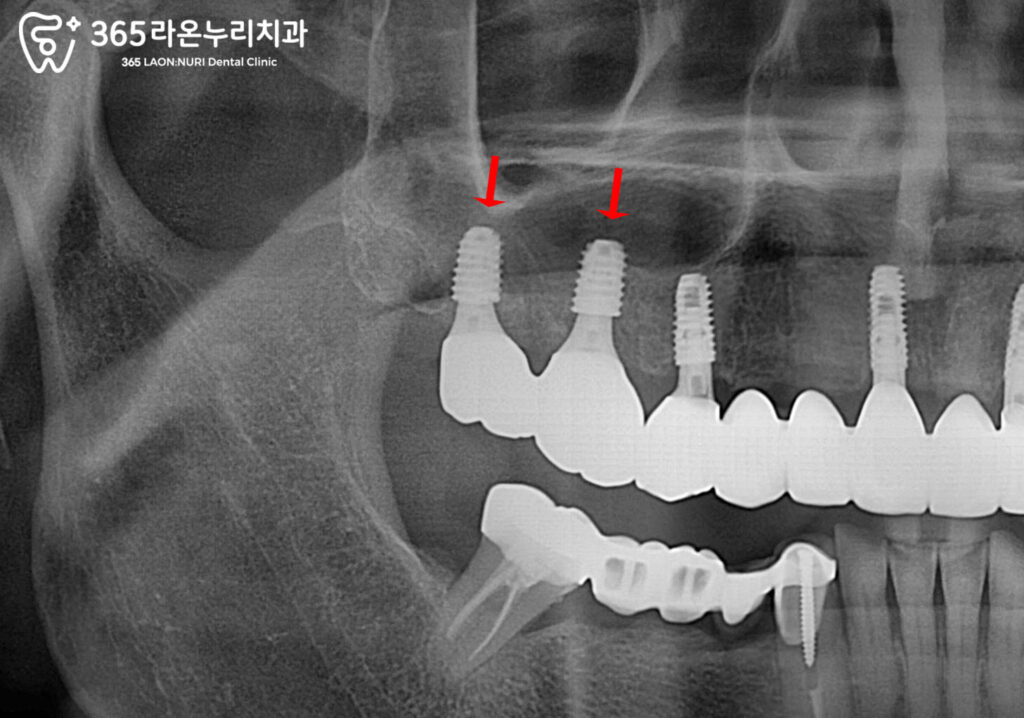

상악동 거상술 및 뼈이식 임플란트 식립

따라서 발치 후 상악동 거상술 및

뼈이식을 통해 부족한 뼈의 양을 보충합니다.

수청동 치과 가 표시한 곳을 보면

새로운 뼈가 하얗게 채워져 있는 것을

볼 수 있으며,

이는 추후 골융합을 통해 단단해지고

임플란트가 안정적으로

자리를 잡을 수 있게 도와줍니다.